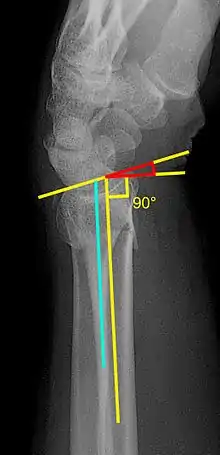

Various kinds of information can be obtained from X-rays of the wrist:[5]

Lateral view

- Carpal malalignment - A line is drawn along the long axis of the capitate bone and another line is drawn along the long axis of the radius. If the carpal bones are aligned, both lines will intersect within the carpal bones. If the carpal bones are not aligned, both lines will intersect outside the carpal bones. Carpal malignment is frequently associated with dorsal or volar tilt of the radius and will have poor grip strength and poor forearm rotation.[5]

- Tear drop angle - It is the angle between the line that pass through the central axis of the volar rim of the lunate facet of the radius and the line that pass through the long axis of the radius. Tear drop angle less than 45 degrees indicates displacement of lunate facet.[5]

- Antero-posterior distance (AP distance) - Seen on lateral X-ray, it is the distance between the dorsal and volar rim of the lunate facet of the radius. The usual distance is 19 mm.[5] Increased AP distance indicates the lunate facet fracture.[8]

- Volar or dorsal tilt - A line is drawn joining the most distal ends of the volar and dorsal side of the radius. Another line perpendicular to the longitudinal axis of the radius is drawn. The angle between the two lines is the angle of volar or dorsal tilt of the wrist. Measurement of volar or dorsal tilt should be made in true lateral view of the wrist because pronation of the forearm reduces the volar tilt and supination increases it. When dorsal tilt is more than 11 degrees, it is associated with loss of grip strength and loss of wrist flexion.[5]

Posteroanterior view

- Radial inclination - It is the angle between a line drawn from the radial styloid to the medial end of the articular surface of the radius and a line drawn perpendicular to the long axis of the radius. Loss of radial inclination is associated with loss of grip strength.[5]

- Radial length - It is the vertical distance in millimetres between a line tangential to the articular surface of the ulna and a tangential line drawn at the most distal point of radius (radial styloid). Shortening of radial length more than 4mm is associated with wrist pain.[5]

- Ulnar variance - It is the vertical distance between a horizontal line parallel to the articular surface of the radius and another horizontal line drawn parallel to the articular surface of the ulnar head. Positive ulnar variance (ulna appears longer than radius) disturbs the integrity of triangular fibrocartilage complex and is associated with loss of grip strength and wrist pain.[5]

Oblique view

- Pronated oblique view of the distal radius helps to show the degree of comminution of the distal end radius, depression of the radial styloid, and confirming the position the screws at the radial side of the distal end radius. Meanwhile, a supinated oblique view of shows the ulnar side of the distal radius, accessing the depression of dorsal rim of the lunate facet, and the position of the screws on the ulnar side of the distal end radius.[5]